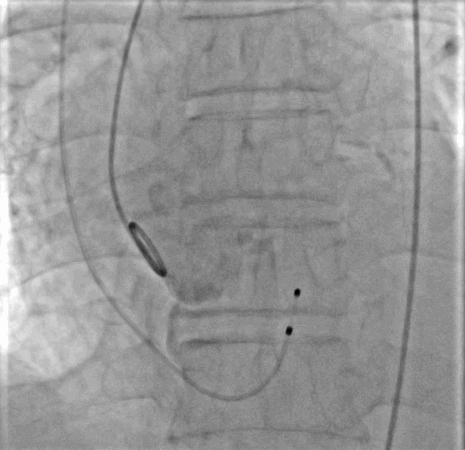

3. 球囊预扩:起搏器180次/分起搏下,取心通医疗Alwide™ 20*40mm球囊扩张病变,扩张充分。撤出球囊。

主动脉根部造影

球囊预扩